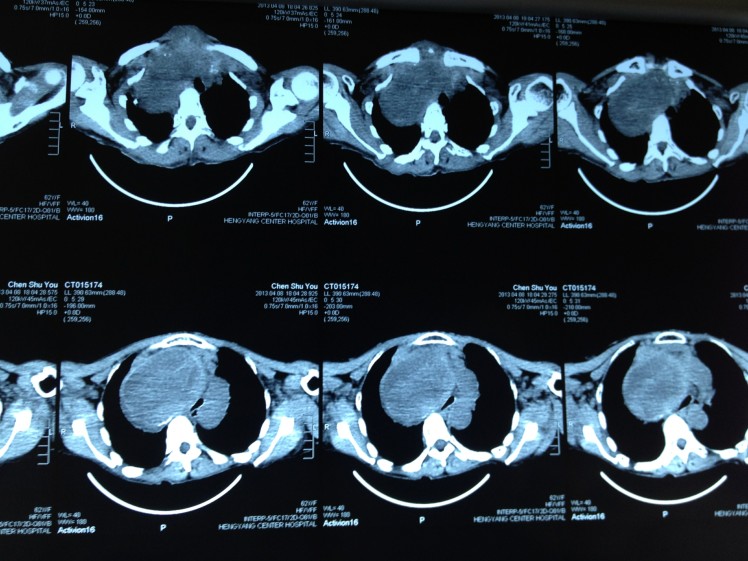

因氣管被甲狀腺巨大腫塊壓迫成“一線天”而險些窒息的陳阿婆,經(jīng)過我院乳甲外科尹軍主任主刀手術(shù),已經(jīng)康復出院。如今,困擾她十多年的胸悶、氣促也已從根本上得到了解決。

4月8日,62歲的陳阿婆因呼吸困難在家中險些窒息而被家人背送我院乳甲外科就診。陳阿婆發(fā)現(xiàn)頸部雙側(cè)腫塊已有30余年,曾就診于省內(nèi)多家大型醫(yī)院,大多專家建議開胸手術(shù),手術(shù)費高達10余萬元,有些醫(yī)院甚至考慮手術(shù)難度大、風險高就干脆拒收入院。我院乳甲外科尹軍主任將患者收住院后,會同醫(yī)務部組織了麻醉科、放射科、胸外科、呼吸內(nèi)科、心內(nèi)科的專家會診,進行術(shù)前討論,制定了周密的手術(shù)方案。

手術(shù)當日,尹軍主任采用沿頸部橫紋作一橫切口,分離左右舌骨下肌瓣,在保留左側(cè)甲狀腺上極一塊如蠶豆大小的正常甲狀腺組織后,對其余雙側(cè)病變部分采取切除、止血、從胸骨下方慢慢剝離的方式,最終成功將巨大甲狀腺腫瘤切除,并將軟化氣管懸吊。整個手術(shù)過程耗時三小時,術(shù)中未輸血,整個甲狀旁腺、喉返神經(jīng)保護良好。術(shù)后病人恢復好,無相關并發(fā)癥,手術(shù)后7日患者康復出院。